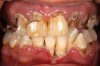

Methadone and other opioids suppress salivary secretion,2 which is mediated by disordered peripheral signaling at parasympathetic muscarinic receptors, or centrally at primary salivary centers.11 Since MMT patients can be often medicated with anti–depressants that further inhibit salivary flow, xerostomia is a common finding. With low saliva flow, generalized bacterial plaque accumulation from poor oral health and buccal cervical highly stained caries of the lower canines and premolars teeth are often present and pathognomonic on MMT patients (Figure 1),6 even though the mechanism of this particular pattern of decay is not fully understood.36

Lewis highlighted that generalized cervical buccal heavily stained carious lesions can be pathognomonic in both methadone and heroin addicts, similar to those who have undergone radiotherapy of the head and neck and those who take multiple xerostomic medications.13 Sheedy compared the detrimental effect of methadone to the oral cavity and coined the term “Methadone Mouth” to characterize the extreme poor oral health conditions of most long–term MMT individuals, particularly with rapid tooth destruction due to aggressive carious activity (Figure 1).24 Methadone Mouth should not be mistaken, however, with “Meth Mouth” (Figure 2 and Figure 3).

Figure 1  Methadone mouth.

Figure 1